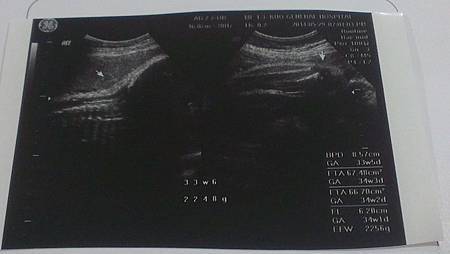

33周又5天產檢情況

體重:64.3kg,寶寶體重:2,248gm

上次在婦幼醫院照,醫師說寶寶的體重是2,200克,當時就覺得有些不可思議,畢竟不太可能兩週內大這麼快,這次在郭綜合照,果然也才2,248克,相當於33W6D的胎兒大小,似乎比較合理。

今天看起來,小馬子整個臉埋在另一邊,看不到,也因為現在比較大隻了,看他整個縮在子宮裡,滿擠的不過羊水量是正常的。